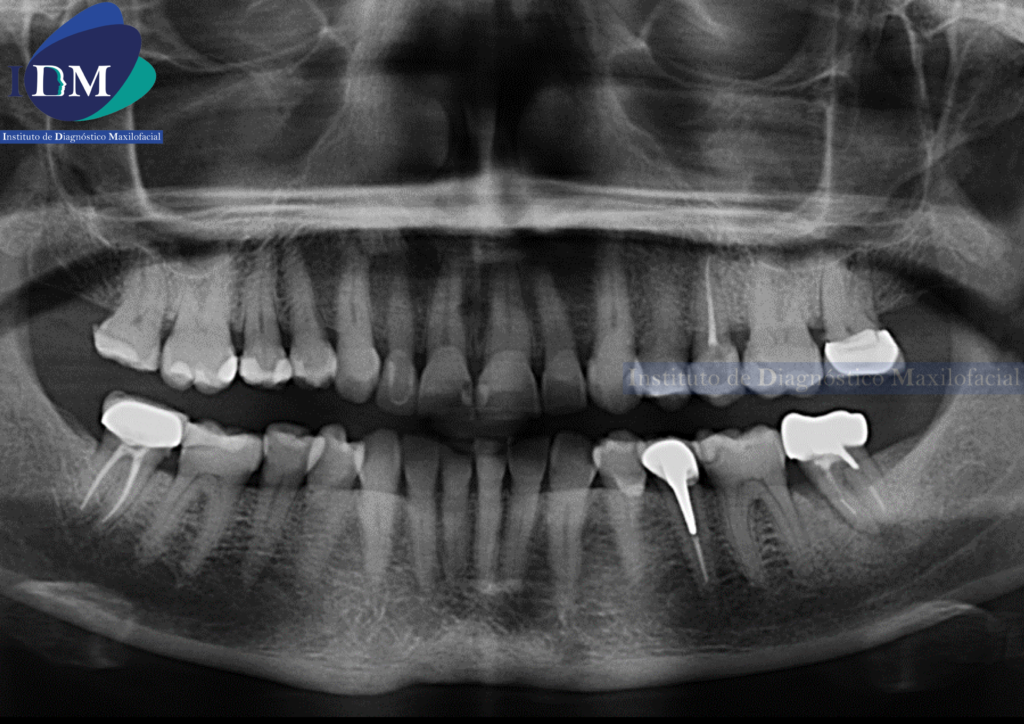

Radiografia Panorámica

A la evaluación de la radiografía panorámica se evidencia una neumatización alveolar de senos maxilares, reabsorción ósea alveolar bimaxilar con múltiples piezas con tratamientos restauradores y de obturación de conductos. Siendo lo mas resaltante un proceso osteolítico perirradicular de la pieza 3.7.